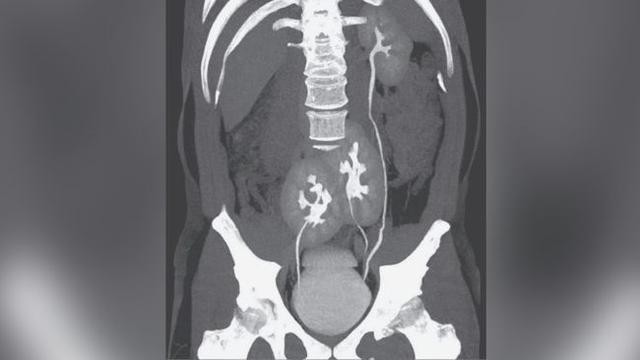

Trang Aboluowang đưa tin, ngày 6/5, một người đàn ông đến Bệnh viện Do Rim ở Sao Paulo, Brazil phàn nàn về chứng đau thắt lưng. Bác sĩ sốc khi phát hiện ra bệnh nhân có 3 quả thận thay vì là 2, đây là một trường hợp rất hiếm gặp.

Tuy nhiên, người đàn ông này không đơn thuần là bị thoát vị đĩa đệm mà có thêm một quả thận không mong muốn. Bác sĩ cho biết bệnh nhân không có bất kỳ triệu chứng bất thường nào về thận và cơ quan này có vẻ như đang hoạt động tốt.

Thông thường, mỗi quả thận được kết nối với bàng quang thông qua một ống niệu quản. Trong trường hợp của người đàn ông này, một quả thận vùng chậu được kết nối trực tiếp với bàng quang thông qua niệu quản. Tuy nhiên, niệu quản của khung chậu thận khác được kết nối với niệu quản của quả thận trái trước khi vào bàng quang.